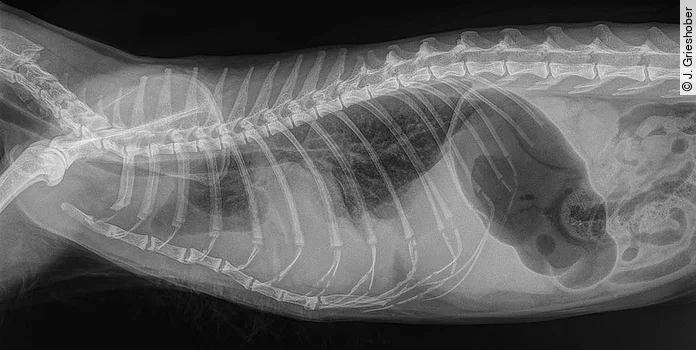

Die erste weiterführende Diagnostik bei Patienten mit Dyspnoe sollte immer ein Thoraxröntgenbild sein. Allein durch die Auskultation von Herz und Lunge kann z. B. nicht eindeutig zwischen Pneumothorax oder Thoraxerguss unterschieden werden.

Thoraxröntgenaufnahmen sind äußerst hilfreich bei der Diagnose und Quantifizierung von Pleuraraumerkrankungen und anderen intrathorakalen Pathologien ([Abb. 1]). Wiederholte Röntgenaufnahmen nach Thorakozentese können von diagnostischem Nutzen sein, um Verbesserungen zu beurteilen und intrathorakale Strukturen besser sichtbar zu machen [6].

Beim Röntgen fertigt man in der Regel als erstes eine laterolaterale Aufnahme in rechter Seitenlage an und – wenn der Zustand des Patienten es zulässt – danach auch eine ventrodorsale oder dorsoventrale Aufnahme. In sehr schwerwiegenden Fällen mit Atemnot kann es jedoch nötig sein, zur Vermeidung von zusätzlichem Stress, auf diese seitliche Lagerung zu verzichten und lediglich eine dorsoventrale Aufnahme in Bauchbrustlage anzufertigen. In jedem Fall gilt: Auf eine ventrodorsale Lagerung sollte eher verzichtet werden, da eine Atemnot in Rückenlage immer deutlich verschlimmert wird [6], [7].